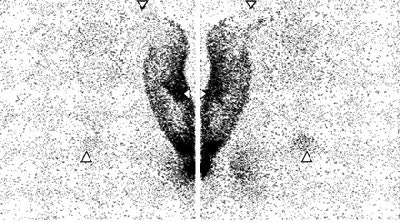

| Lymphoscintigraphy images of upper limb and torso in female patient. Downward-pointing arrowheads = shoulders, lateral arrowheads = elbows, upward-pointing arrowheads = pubic bone. Images obtained 52 and 48 minutes after intradermal (above) and subcutaneous (below) injections, respectively. There is greater clarity and earlier visualization of lymphatic structures after intradermal injection. Left and right panels are posterior and anterior images, respectively. |

"Lymphatic structures were visualized earlier and with unequivocally greater clarity after intradermal injection compared with subcutaneous injection in all six patients," the authors wrote. In addition, discrete lymphatic vessels in the upper arm were seen in five patients after intradermal injection.

No clear difference was seen between the two techniques with respect to activity outside the depot, they stated. However, arm activity steadily increased after subcutaneous injection, while after intradermal detection, arm activity reached a peak and then declined.